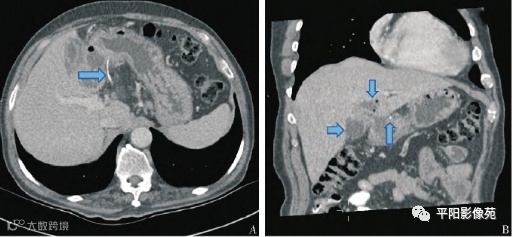

图1 A:胃幽门区鱼刺,刺破胃壁突入腹腔;B:肝左叶脓肿

鱼刺的影像特点:

条形高密度,形状规则,边界清晰

CT值约100~200HU左右,低于人类骨骼CT值的300~800 HU

局部可继发炎症,进而形成脓肿

图2 鱼刺穿透胃壁刺入肝脏,伴发脓肿